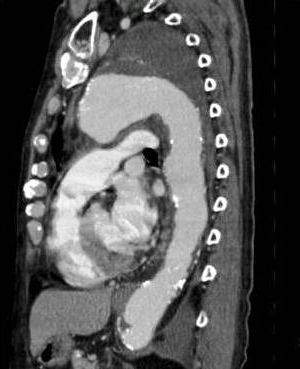

巨大な破裂性遠位弓部大動脈瘤(術前)

頸部分枝の再建をしてステントグラフトを上行大動脈から下行大動脈まで挿入した(ハイブリッド手術後)